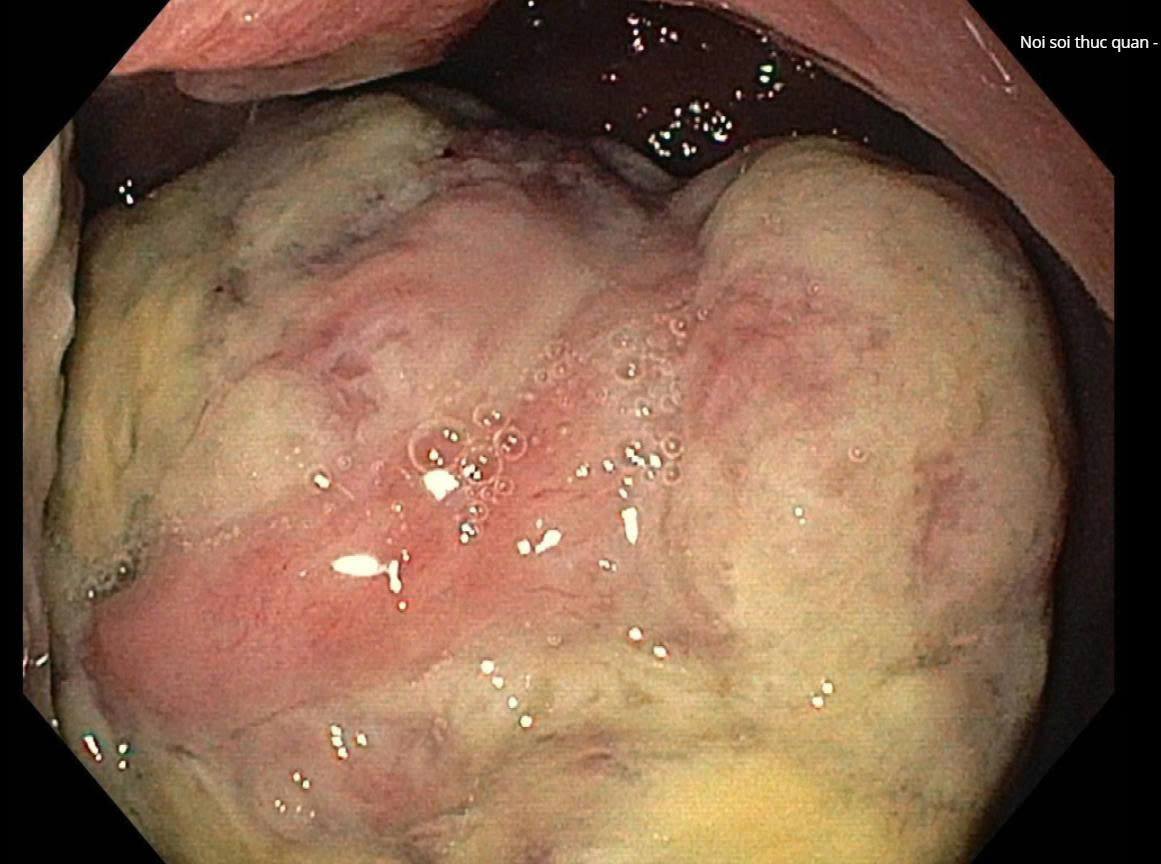

Hình ảnh nội soi khối ung thư hang vị dạ dày

Người bệnh N.T.N (83 tuổi, Hưng Yên) nhập viện Bưu điện trong tình trạng đau tức vùng thượng vị, chậm tiêu, gầy sút cân rõ rệt trong khoảng một tháng gần đây. Qua thăm khám lâm sàng, nội soi dạ dày, sinh thiết tổn thương và chụp cắt lớp vi tính ổ bụng, các bác sĩ xác định người bệnh bị ung thư hang vị dạ dày, khối u đã xâm lấn qua thành dạ dày và di căn đến một số hạch bạch huyết vùng lân cận.